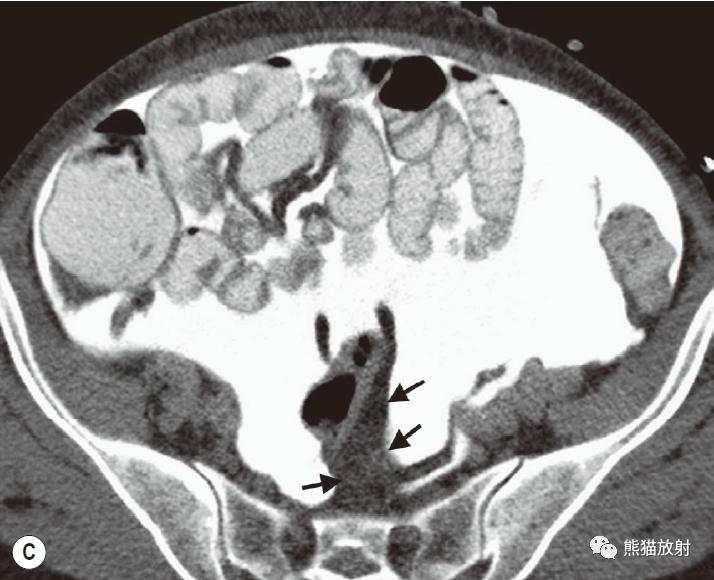

腹内疝:内脏通过腹膜或肠系膜孔突出形成。

包括:十二指肠旁(53%)、盲肠周围(13%)、Winslow孔(8%)、肠系膜和结肠系膜(8%)、乙状结肠间(6%)、吻合口后(5%)疝。

肠系膜疝。 扩张、充满液体的小肠襻丛位于前腹壁下的升结肠侧旁(箭),取代网膜脂肪。充盈的血管及邻近肠系膜模糊,折射了小肠绞窄性梗阻。